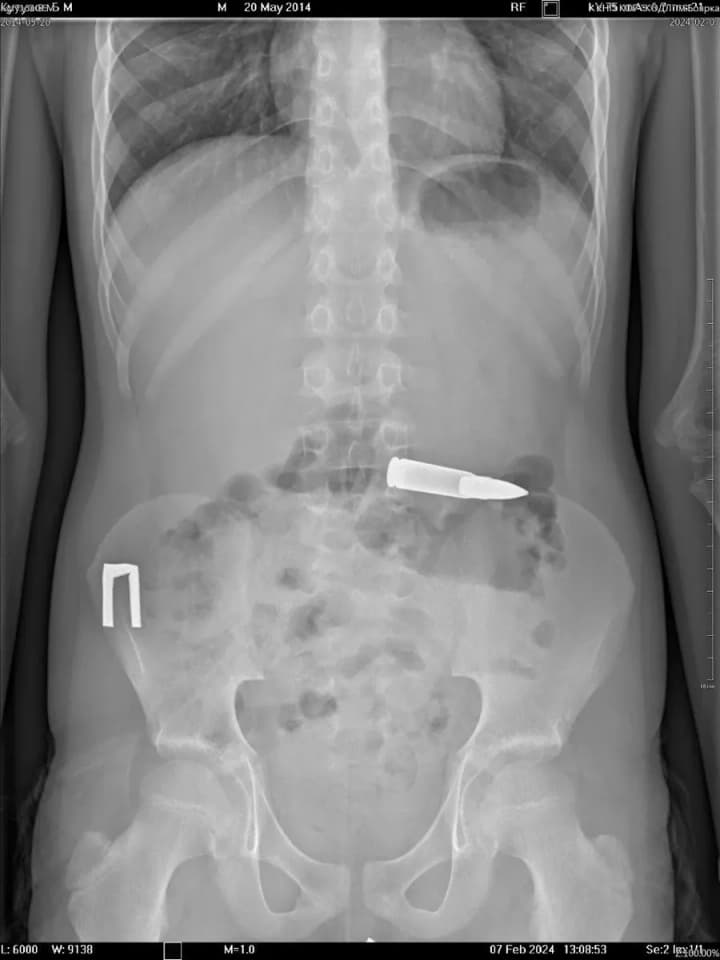

In Kyiv region, a boy swallowed a bullet. Doctors managed to successfully remove the foreign object. UNN reports this with reference to the press service of the Kyiv Regional Children's Hospital.

First of all, the doctors took an X-ray and located the object to avoid complications. Nothing interfered with the intervention, so the doctors successfully removed the object.